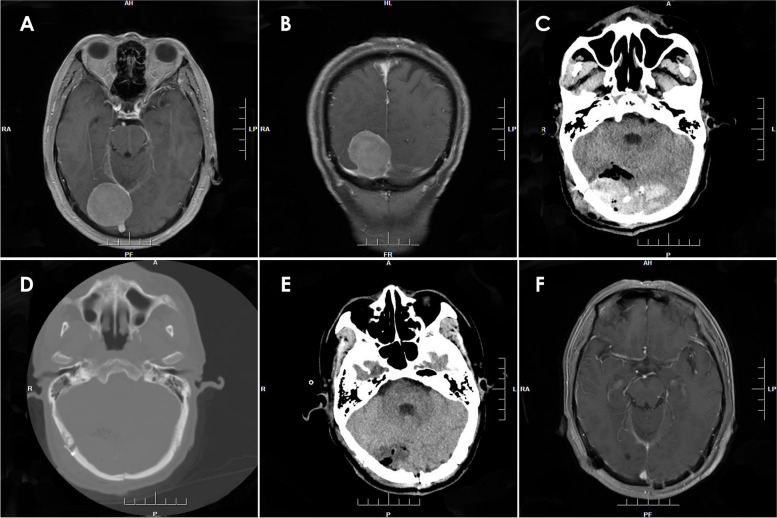

Results: Twenty-five patients (10 males, 15 females; median age 42 years, range 11-61 years; median medical history 27 months, range 1-96 months) were enrolled in the study. Regarding tumor location, 16 cases exhibited supratentorial brain tumors, 4 cases had infratentorial brain tumors, 2 cases of tumors occurred in the petroclival region, 2 cases in the peritorcular region, and 1 case in the pineal region. Four of these cases were complicated with supratentorial hydrocephalus. The 25 cases in this study were classified into four types based on location. Type 1 refers to EDHs that occur at the adjacent site of the operative field without involvement of the surgical area. Type 2 includes hematomas that occur at the adjacent site of the surgical area and the surgical area. Type 3 includes EDHs that occur in distant areas, and type 4 involves EDHs in the surgical field. The numbers of cases of types 1, 2, 3, and 4 PEDHs were 16, 2, 3, and 4 cases, respectively. Most PEDHs were associated with reduced ICP after craniotomy due to intracranial tumor resection and substantial loss of CSF. All patients achieved satisfactory outcomes after hematoma evacuation.